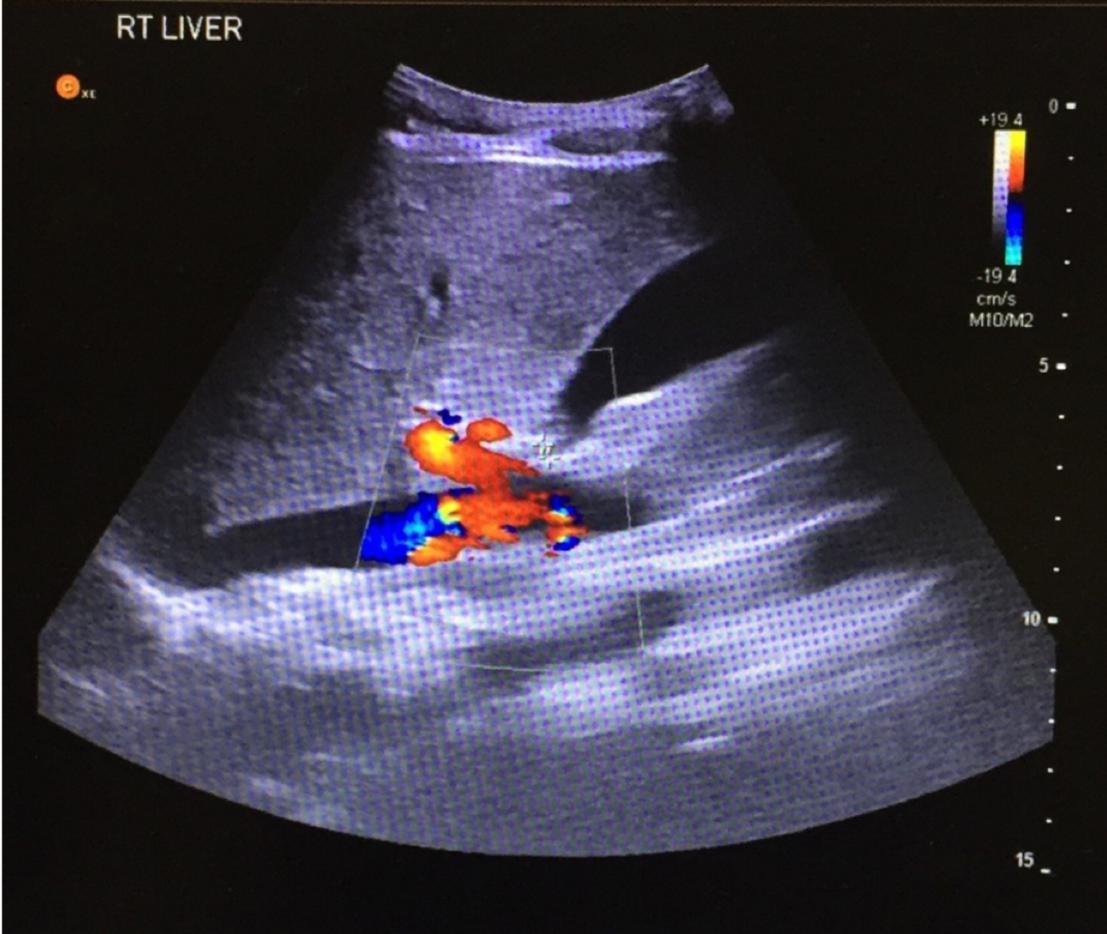

起初,考虑卵巢囊肿,然而尿液浸润阴性和妊娠试验阴性,排除妇科疾病。血液检查结果患者并无明显异常。腹部超声提示阑尾腔增粗,局部渗出,证实了急性阑尾炎的诊断,但特殊的是阑尾解剖变异,位于右肝下水平,如图1所示,考虑肝下阑尾。

图1 超声提示肝脏水平可见阑尾,直径约0.6cm